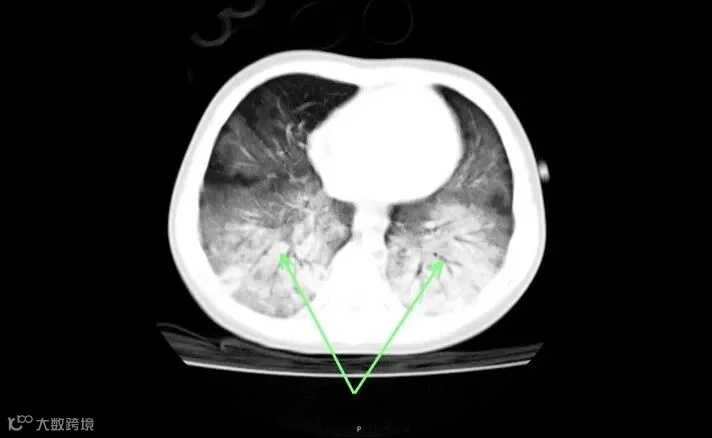

1岁娃因误食电蚊香液

被紧急送医,住进ICU

宝宝一阵咳嗽

吐了一点点出来

但是,人逐渐变得软软的

四肢无力

经呼吸道吸入后可能出现

头痛、头晕、乏力,恶心、呕吐等症状

一般对于人体而言

是低毒性或者是微毒性

如果不慎误服了

可能有毒的化学品

应尽早就医

越早越好!